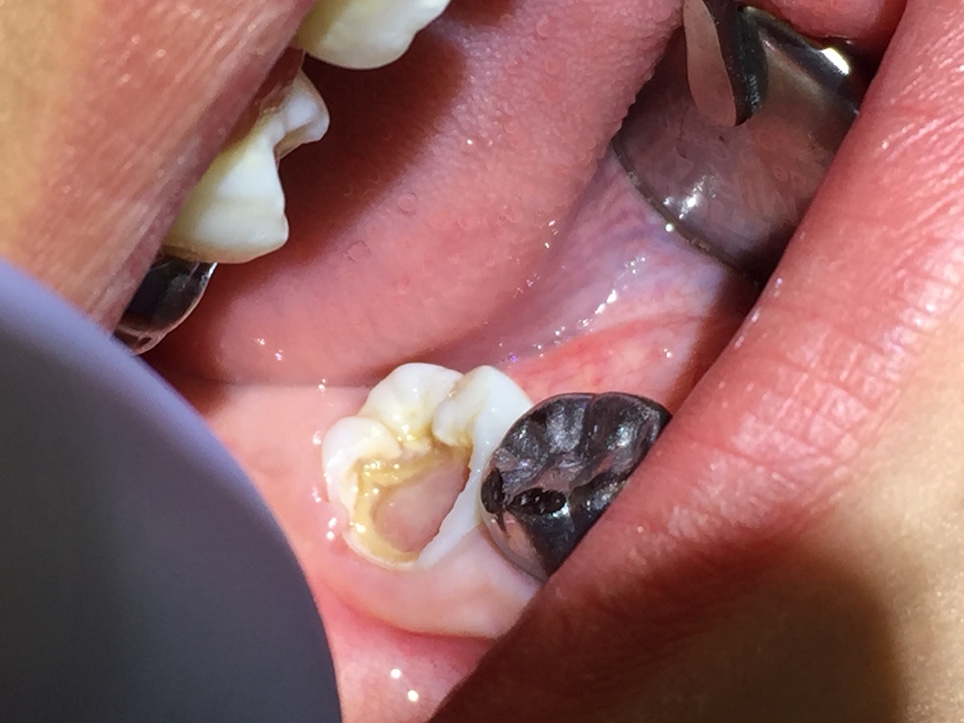

Asymptomatic irreversible pulpitis is a vital pulp that is incapable of healing, and endodontic treatment is consequently indicated. Although asymptomatic irreversible pulpitis is actually a histologic diagnosis to determine the inflammatory extent of the pulp, clinical examples of this diagnosis include a pulp polyp and internal resorption (Figure 1).

Fig 1. A pulp polyp is a clinical example of an asymptomatic irreversible pulpitis diagnosis.

Figure 1